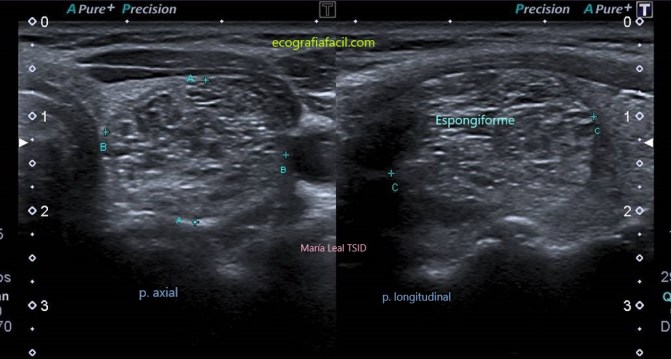

ESPONGIFORME:

Nódulo espongiforme.